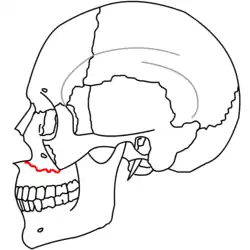

- The Le Fort II fracture (pyramidal fracture) includes a fracture line from one of the lateral vertical buttresses across the maxillary bone, extending into the inferior orbital rim and crossing the midline (either through the nasal root or nasal bones).[5] The defining feature of this fracture pattern is involvement of the inferior orbital rim.[5] When viewed from the front, this fracture is classically shaped like a pyramid.